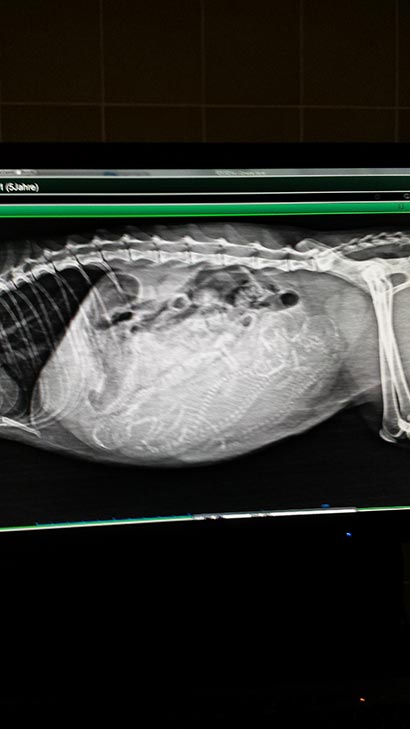

Da es Caline nicht sehr gut ging haben wir Sie in eine Tierklinik gebracht.

Dort hat sich herausgestellt das sie hochschwanger war. Die Kleinen mussten per Kaiserschnitt geholt werden, da die Gebärmutter so voll war und gegen den Magen gedrückt hat.

Da Caline keine Milch hat wurden die Kleinen erfolgreich einer anderen Mutterkatze "untergeschoben" . Caline hat noch eine Schnupfeninfektion und kann hoffentlich bald die Tierklinik verlassen. Über finanzielle Unterstützung würden wir uns sehr freuen. |